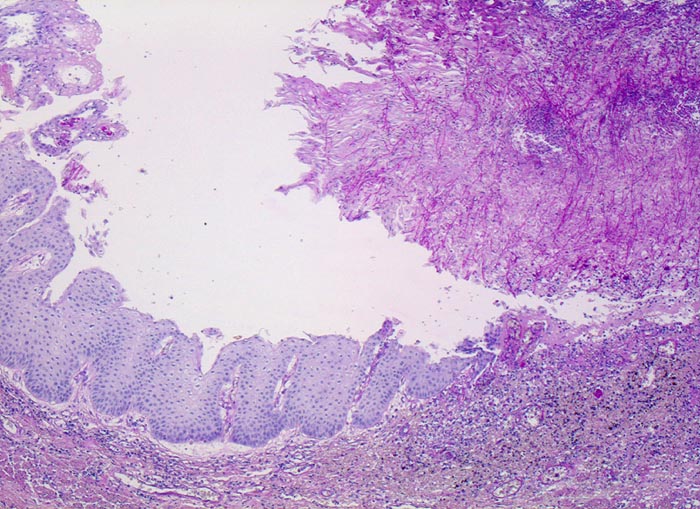

Endoskopisch finden sich abstreifbare weissgelbe krümelige Plaques, welche keine Prädilektionsstelle zeigen. Die Schleimhaut kann erodiert oder ulzeriert sein. In Klumpen von nekrotischen Plattenepithelzellen lassen sich mikroskopisch oft Sporen und Pseudohyphen nachweisen. Die Pseudohyphen wachsen oft senkrecht zur Epitheloberfläche. Besonders gut sichtbar werden die Pilze in der PAS oder Grocott Färbung. Zusätzlich besteht eine aktive Ösophagitis mit Infiltration der oberflächlichen Plattenepithelschicht durch neutrophile Granulozyten. Zahlreiche neutrophile Granulozyten in einem Ulkus weisen auf eine Soorösophagitis. Bei viral bedingten Ulzera (Herpes, CMV) prädominieren Makrophagen.

• Teils ulzerierte, teils erodierte Ösophagusmukosa.

• Die Pseudomembran über der ulzerierten Schleimhaut setzt sich zusammen aus einem dichten Netzwerk PAS positiver Soorpseudohyphen und ovale aussprossende Sporen, nekrotischem Plattenepithel, Fibrin und neutrophilen Granulozyten.

• Die Pseudohyphen infiltrieren das Plattenepithel.